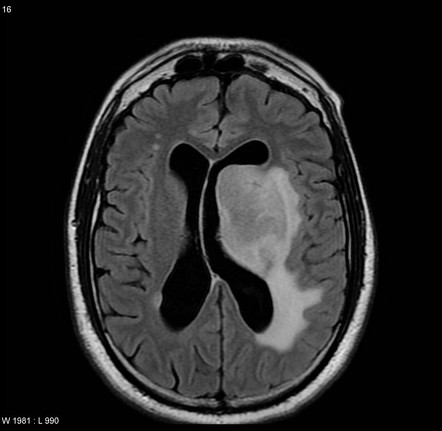

患者出现进行性和相对快速的局灶性神经症状进展。超过三分之二的患者存在局灶性神经功能缺损,超过40%的患者有神经精神症状。其他症状包括颅内压升高、癫痫发作和视觉障碍。

- 2. 磁共振成像与对比是较敏感的影像学检查方法。